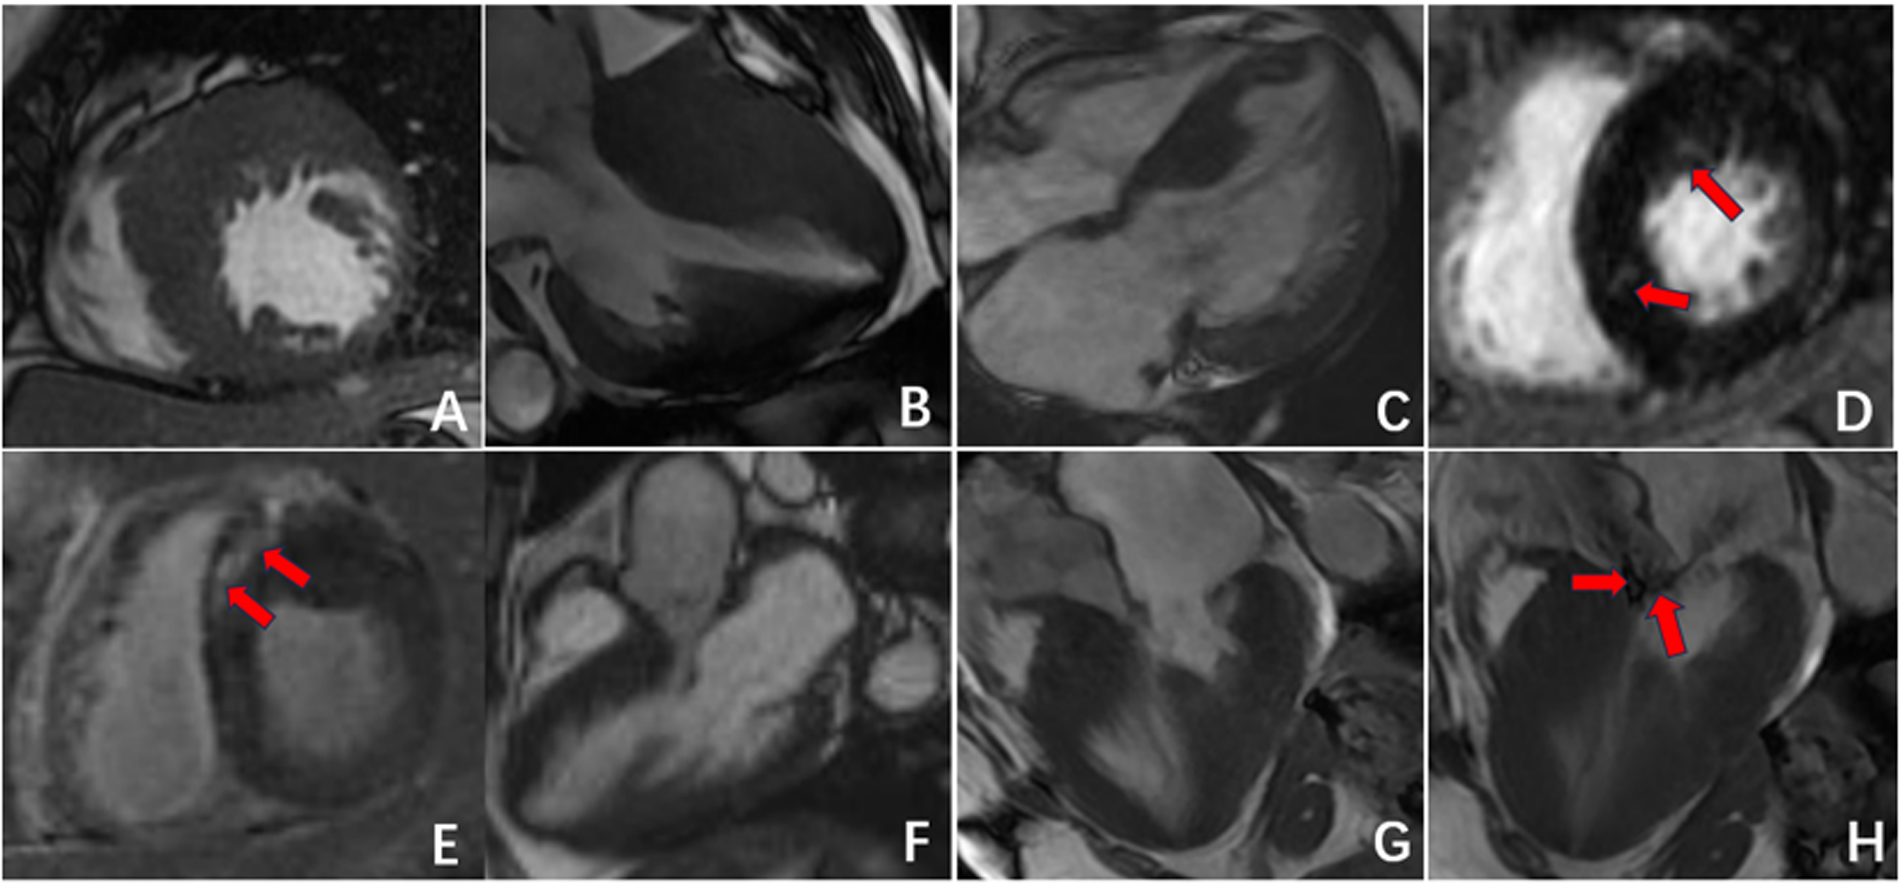

Figure 2

Radiographic findings of CA. (A,B) Symmetric myocardial hypertrophy; (C,D) pleural effusion and pericardial effusion; (E,F) subendocardial enhancement (red arrow); (G) transmural delayed enhancement pattern indicating diffuse myocardial infiltration; (H,I) delayed enhancement affected the left atrium, right atrium, and right ventricle; (J,L) “dark blood pool imaging” and “chaotic sign”.

Furthermore, in 15 patients (50%) in the CA group, delayed enhancement not only affected the left ventricular myocardium but also involved the left atrium, right atrium, and right ventricle. In contrast, delayed enhancement in the HCM group did not extend to other cardiac chambers. In 10 patients (33.3%) in the CA group, a “dark blood pool imaging” phenomenon was observed, in which the signals of the blood pool and myocardium were indistinguishable after delayed enhancement, presenting a typical “chaotic sign”. This feature has specific diagnostic value for CA (Table 2, Figure 2, Figure 3).

Both CA and HCM can present with left ventricular myocardial hypertrophy and increased mass, but their underlying pathophysiology and imaging features are distinct. CA occurs primarily due to diffuse deposition of amyloid substances in the left ventricle, leading to symmetrical and uniform thickening of the myocardium (14). In contrast, HCM is characterized predominantly by asymmetrical hypertrophy of the left ventricular myocardium, especially hypertrophy of the interventricular septum myocardial cells and fibrosis in the hypertrophic myocardial area (15–17), sometimes resulting in signs of outflow tract narrowing and obstruction (18). Additionally, CA patients often have pleural effusion or pericardial effusion, which may be related to heart failure or amyloid substance deposition (19). These overlapping clinical manifestations contribute to a high rate of misdiagnosis, underscoring the value of advanced imaging techniques for differentiation.

The results of this study indicate that delayed enhancement CMR patterns can serve as a useful method for distinguishing between CA and HCM. The enhancement pattern of CA is characterized mainly by subendocardial diffuse enhancement and transmural enhancement, findings that have been widely described in previous studies of cardiac amyloidosis using late gadolinium enhancement (20, 21). This enhancement pattern may be related to the deposition pattern of amyloid substances, which initially deposit subendocardially with blood flow distribution and progressively involve the entire myocardium, manifesting as transmural enhancement as the disease progresses. Additionally, when amyloid substances are deposited in other cardiac chambers, they can manifest as enhancement of varying degrees in the left atrium, right ventricle, and right atrium. Some researchers have proposed that the delayed enhancement imaging features of CA are related to the deposition of amyloid substances and thus correspond to CA prognosis (22–24). In contrast, delayed enhancement in HCM presents mainly as patchy enhancement in areas of hypertrophic myocardium, especially in the middle layer of the interventricular septum. In patients with CA, a distinctive phenomenon, termed the “chaotic sign”, is frequently observed on delayed enhancement images. We define this sign as a loss of normal contrast between the blood pool and myocardium, producing a diffusely hypointense ventricular cavity with blurred endocardial borders. This appearance reflects markedly altered gadolinium kinetics due to diffuse amyloid infiltration and rapid clearance of contrast from the blood pool. Similar “dark-blood” or “non-nullable myocardium” findings have been described in previous studies of cardiac amyloidosis (25, 26). Left ventricular systolic and diastolic deformation is achieved through the combined action of the three layers of myocardial fibers: subendocardial myocardium, mid-myocardium, and subepicardial myocardium. Each layer of myocardial fibers affects strain in different directions according to the angle of orientation (27, 28). The subendocardial myocardium, which is parallel to the long axis of the heart, affects mainly longitudinal strain, whereas the mid-myocardial fibers, oblique to the heart's outer surface, affect mainly circumferential strain; radial strain is affected by the combined action of all myocardial layers (29). In CA patients, amyloid proteins are deposited in the subendocardial myocardium in the early stages of the disease, predominantly affecting longitudinal strain. Therefore, the decreased longitudinal strain of the left ventricle is the most sensitive indicator for evaluating myocardial amyloidosis (30, 31). The results of this study indicate that, compared with the HCM and control groups, the CA group exhibited significantly reduced GLS, suggesting more pronounced damage to the subendocardial longitudinal myocardium in CA patients. Additionally, the GRS and GCS values in CA patients were significantly lower than those in the HCM and NC groups. The variation in these parameters may suggest that amyloid substance deposition gradually affects the mid-myocardium and subepicardial myocardium, indicating further deterioration in CA.